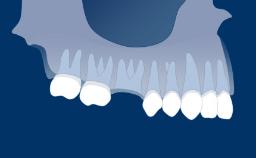

Anatomy with Relevance to Implant Surgery

The understanding of the facial anatomy with its associated osseous and neurovascular structures is essential to the implant surgeon. During treatment planning and implant surgery, certain critical landmarks and boundaries must be respected. The anatomy of the maxilla and mandible is complex, and the implant surgeon should also keep in mind that many variations exist between individuals. The aim of this module is to review the basic anatomy of the facial region and to provide an overview of the important structures involved in implant dentistry in the average adult patient.